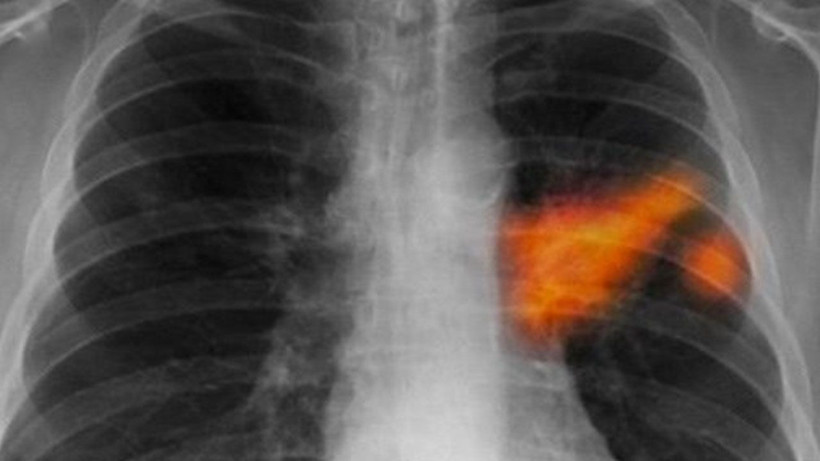

Türkiye'de her yıl 45 bin yeni vaka! Bu illere dikkat: Risk daha fazla! - Resim: 2

HER YIL DÜNYADA 2 BUÇUK, TÜRKİYE'DE YAKLAŞIK 45 BİN YENİ VAKA

Türk Tıbbi Onkoloji Derneği Üyesi ve Medikal Onkoloji Uzmanı Doç. Dr. Şahin Laçin, her yıl dünyada 2,5 milyon, Türkiye'de ise yaklaşık 45 bin yeni vakanın ortaya çıktığını ve bu verilerin akciğer kanserini özellikle erkeklerde ilk sıraya, kadınlarda da üst sıralara taşıdığını söyledi.